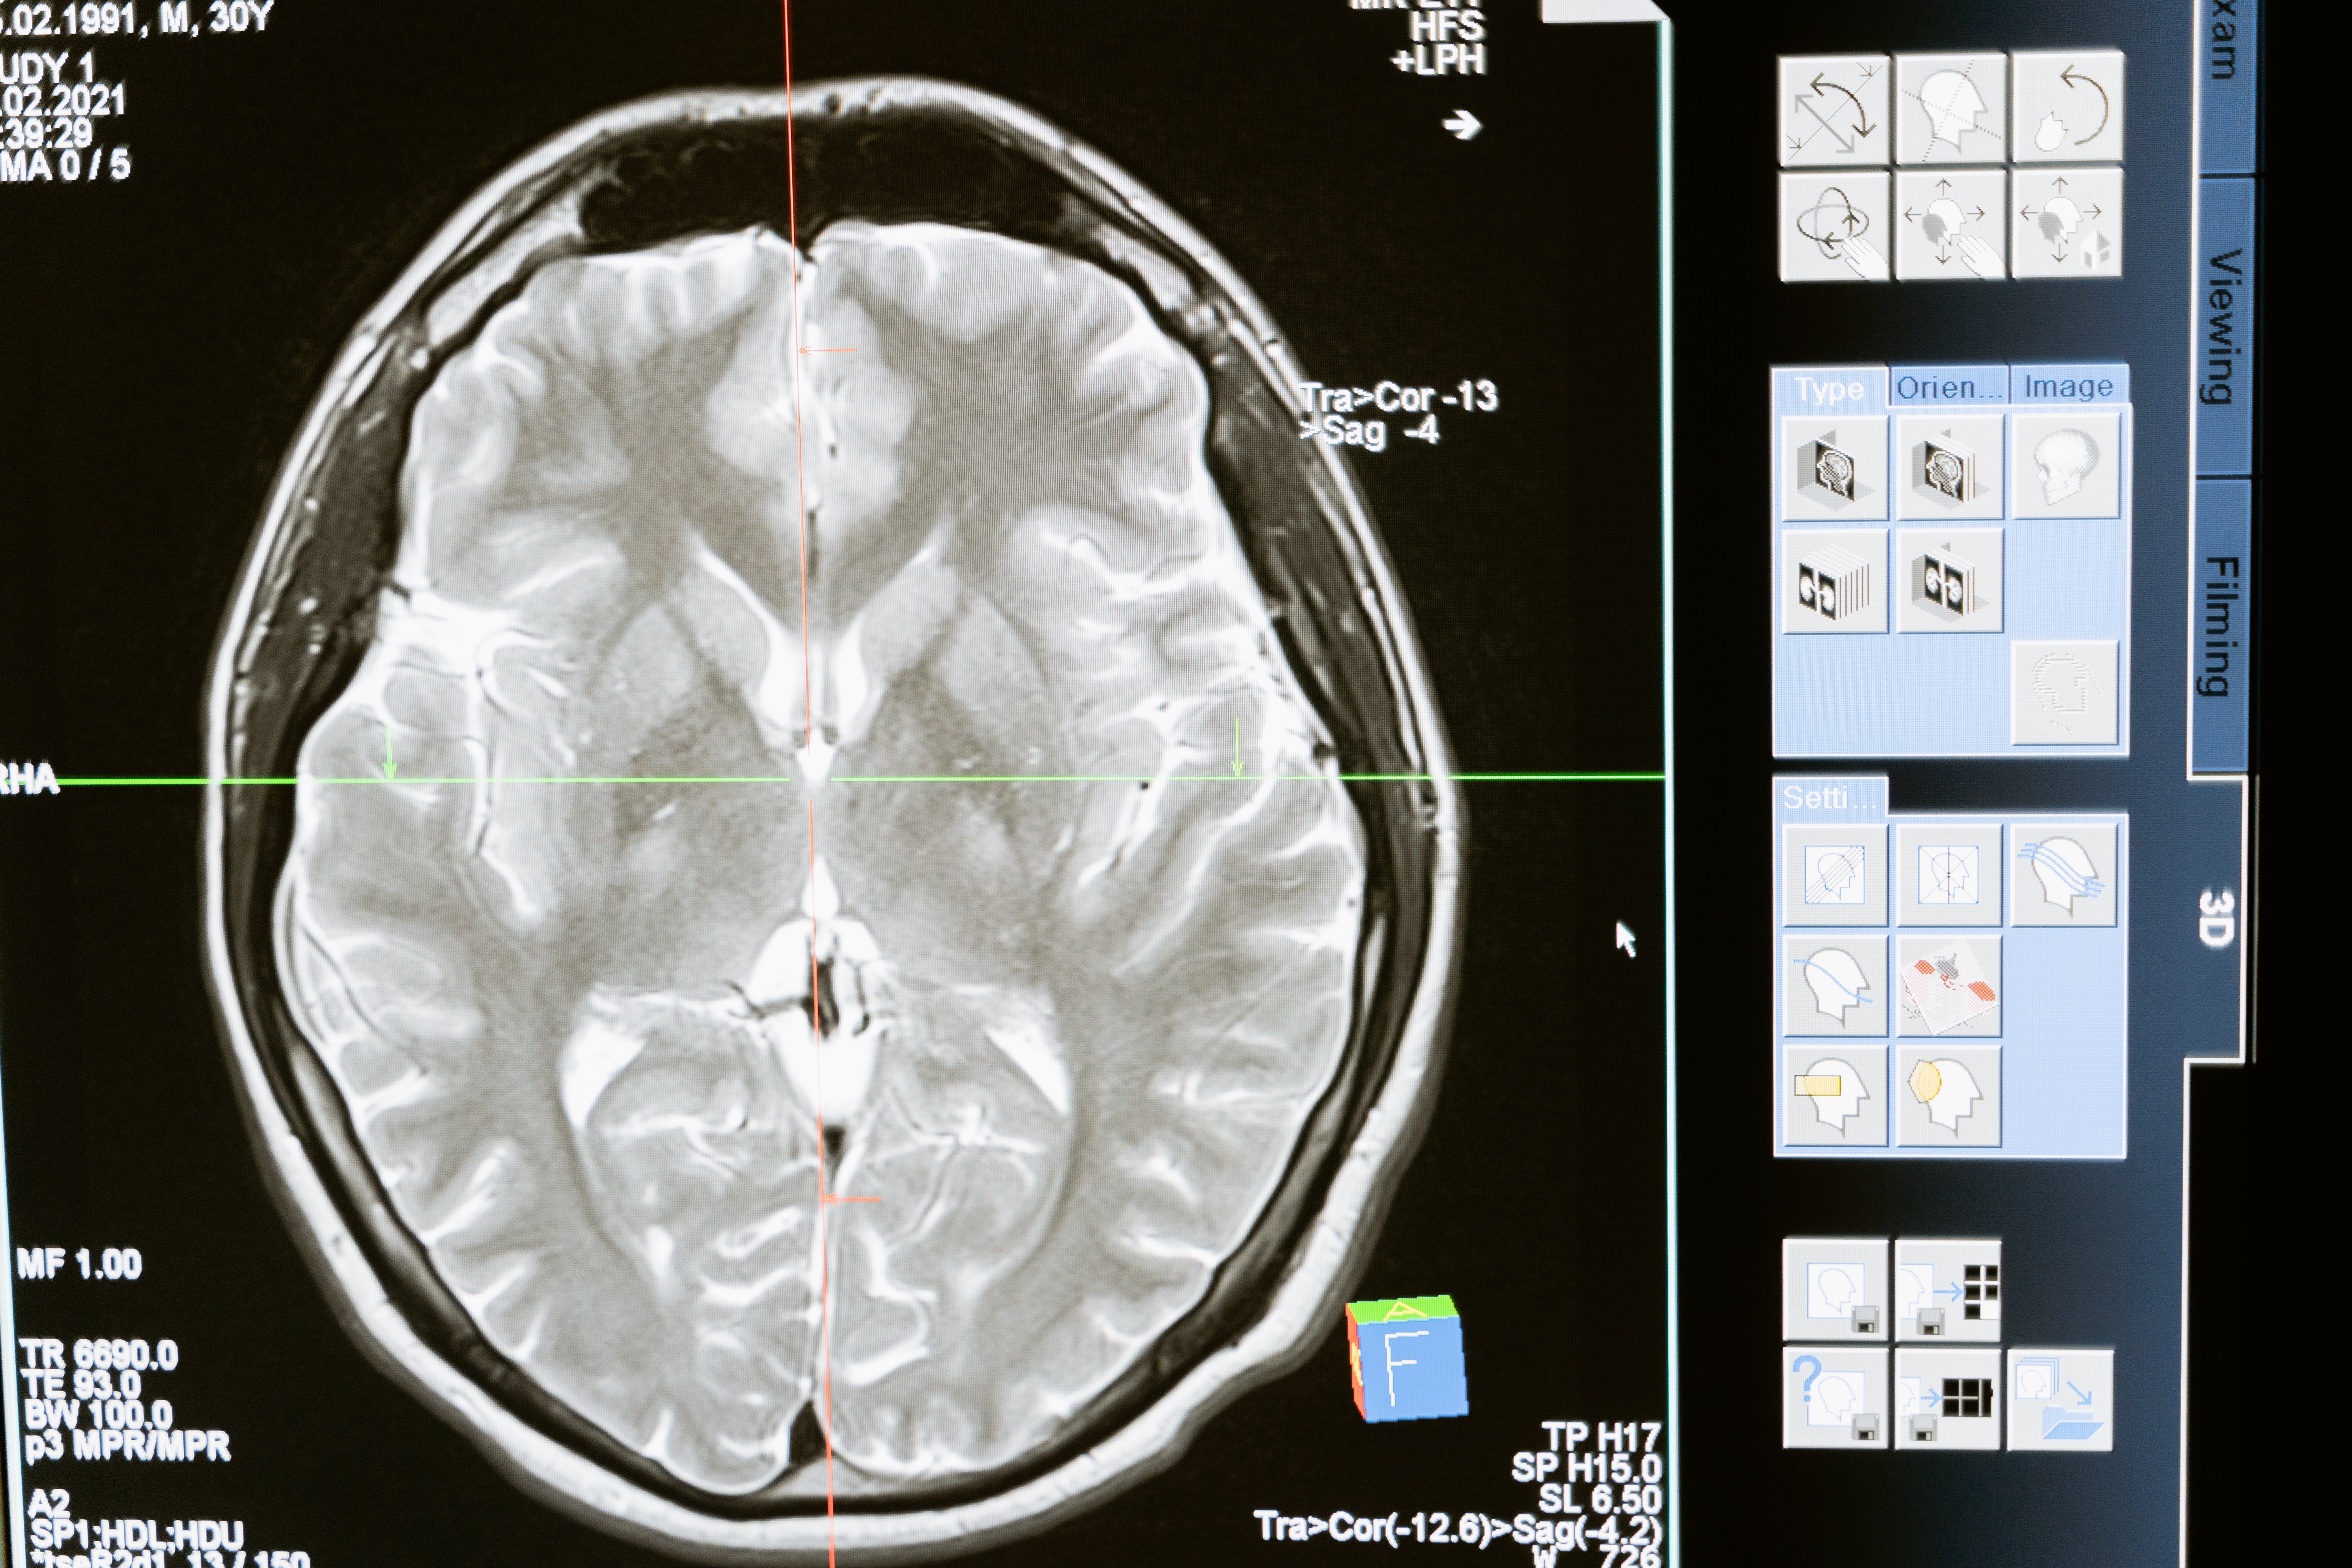

뇌의 무게는 우리 몸의 2%밖에 차지하지 않지만, 허파로 들이마시는 산소의 20%, 심장이 펌프질 하는 혈액의 15%를 사용한다고 합니다. 그래서 중추기관으로 불립니다.

뇌출혈은 혈관 벽에 갑자기 높은 압력이 가해져 터지는 것을 말합니다. 뇌출혈은 크게 두가지고 나뉩니다. 뇌 안에서 터지느냐? 혹은 지주막(거미막)에서 터지느냐입니다. 강수연 씨의 사인은 뇌 안에서 터져서 발생한 뇌 내출혈(I61)입니다.

뇌 내출혈이란 혈압으로 인해 뇌 안에 미세혈관들이 터졌을 때 나타납니다. 즉, 실핏줄이 머릿속에서 터지는 것을 말합니다. 실핏줄이 터지는 대부분의 이유는 그 작은 혈관이 혈관의 압력을 못 이겨서 발생합니다. 즉 뇌내출혈의 대부분의 원인은 고혈압입니다.

예를들어 보겠습니다. 연두부를 뇌라고 생각하고 탁구공을 터진피라고 가정해 보겠습니다. 뇌 안에 공간은 정해져 있는데 탁구공을 쑤셔 넣은 상황을 생각해 보면 이해가 빠릅니다. 탁구공이 들어갈수록 뇌 압력이 높아집니다. 막약에 터진 피의 양이 탁구공이 아니라 농구공만 하다면 어떨까요? 뇌내출혈에서 가장 위험한 것은 바로 뇌 내에 압력이 높아지는 것입니다. 강수연 씨의 경우에도 피가 너무 많이 터져 압력이 높아져 우리 몸의 호흡을 담당하는 척수를 압박하였다고 합니다. 그래서 제대로 수술도 해보지 못했다고 합니다.